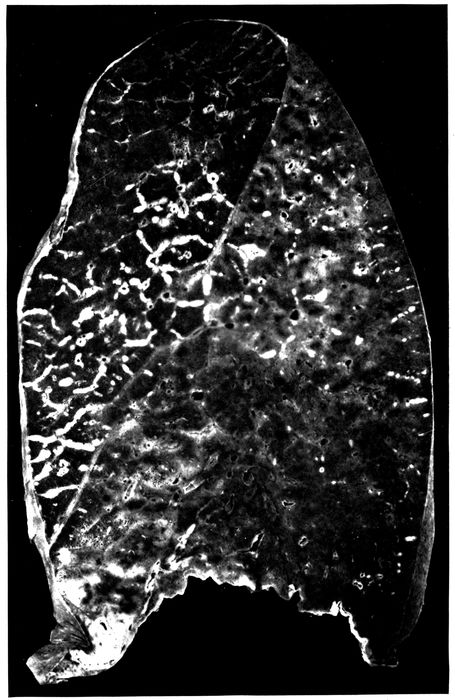

| 2. | Acute bronchopneumonia with nodules of peribronchiolar consolidation and purulent bronchitis | 167 |

| 3. | Acute bronchopneumonia with peribronchiolar consolidation | 169 |

| 4. | Acute bronchopneumonia with peribronchiolar consolidation | 170 |

| 5. | Bronchopneumonia with hemorrhagic peribronchiolar consolidation | 174 |

| 6. | Acute bronchopneumonia with confluent gray lobular consolidation in lower part of upper lobe and hemorrhagic peribronchiolar pneumonia in lower lobe; purulent bronchitis | 180 |